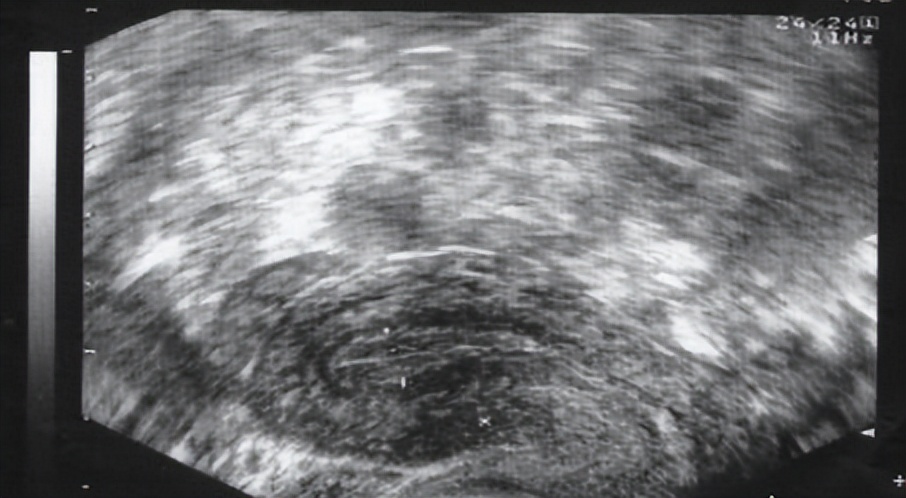

一般在月经周期第10天左右开始监测,观察卵泡直径的变化,在排卵前4天的卵泡直径平均每天约增1.5mm,在排卵前卵泡成熟约18-22mm,排卵后卵泡消失,连续监测可见在排卵前卵泡不断长大,当最大的卵泡消失时,提示发生排卵。

第3次B超:月经第13天左右,恰恰在排卵前,这时B超会出现卵泡周围透声环,卵泡应该在24小时内排卵。

第4次B超:刚刚排卵后第14天左右,卵泡已经消失或显著缩小5mm以上,子宫直肠隐窝内可见液性暗区4-6mm,甚至更多。